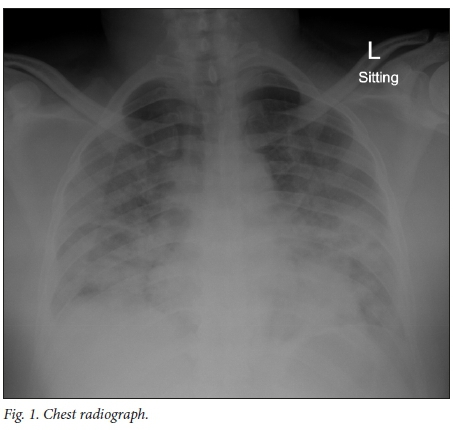

A chest radiograph (Fig. 1) demonstrated diffuse bilateral ground-glass infiltrates, with patchy areas of consolidation. A full blood count revealed lymphopenia (white blood cell count 0.56 χ 109/L, normal range 1.4 - 4.2 χ 109/L) and a mildly reduced platelet count (166 χ 109/L, normal range 171 - 388 χ 109/L), with an absolute CD4+ cell count of 78 cells^L. The C-reactive protein level was 225 mg/L (normal <10 mg/L), and the procalcitonin (PCT) level 0.97 μg/L (normal <0.1 μg/L). He had mild hepatic transaminitis and normal kidney function.

Our patient presented relatively late in the course of disease, and in retrospect the initial case definition should have included people who have close contact with international travellers. It is unclear whether the severity of our patient's presentation can solely be attributed to the normal progression of COVID-19 in an immunocompromised patient or whether it was complicated by a bacterial infection (initial raised PCT which gradually dropped to 0.46 μg/L on antibiotic treatment). In a resource-constrained setting, it is common practice to ration access to intensive care, particularly in patients with HIV infection who are not established on ART and whose case is complicated by AIDS-defining illnesses, owing to their historical poor prognosis.[4] At present we do not know what the outcomes of critically ill HIV/SARS-CoV-2 co-infected patients will be. When there is widespread community transmission of SARS-CoV-2, with high numbers of severely ill patients requiring ICU care, distinguishing between COVID-19, PCP and other AIDS-defining illnesses at the outset will become of critical importance. In PLHIV and other immunocompromised populations, PCP remains an important differential diagnosis in patients with CD4+ cell counts <200 cells/μL who present with progressive lower respiratory tract symptoms, including a dry cough, shortness of breath, hypoxaemia and bilateral ground-glass infiltrates on radiological imaging. However, none of these features are specific for PCP, and they may also be consistent with COVID-19 pneumonitis. In our setting, the diagnosis of PCP in HIV-infected patients is made on clinical and characteristic chest radiographic features, without further extensive diagnostic testing. During the COVID-19 pandemic, we recommend further diagnostic testing when PCP is considered. This includes an expectorated sputum sample[5] (or a tracheal aspirate in the intubated patient) for PCR or immunofluorescence testing, and also a serum sample for beta-D-glucan. Owing to the potential for generating aerosols, obtaining an induced sputum sample for PCP testing is currently not advised.[6]